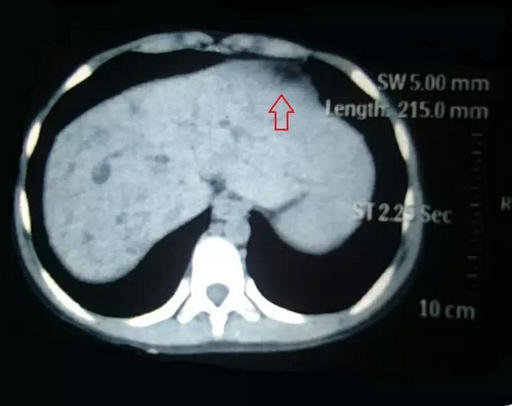

李晓勇教授及主管医生陈艳军副主任医师热情地接待了小夏及家人,在全面了解病史、详细检查之后,小夏的病情让经历了种种疑难病症的李晓勇教授陷入了深思。小夏的肝脏明显增大,弥漫性肝硬化,肝中叶肿物较大,80mm×70mm左右,并且肿物与左右肝管关系密切,门静脉主干及左右支明显受压。

术前肝肿瘤